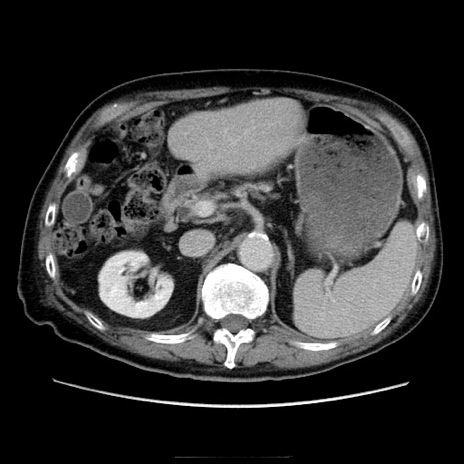

症例21(横断像)

【症例】70歳代男性

【主訴】腹痛

【現病歴】肝硬変・肝細胞癌にてかかりつけの方。約9時間前に食後より腹痛出現。症状が徐々に増悪し、嘔吐出現したため来院。

【既往歴】肝硬変、肝細胞癌(RFA、TACE後)

【身体所見】意識清明、表情苦悶様、BT 36℃、BP 129/78mmHg、P 88bpm、SpO2 97%(RA)、右上腹部から心窩部にかけて圧痛あり、反跳痛なし、筋性防御あり。

【データ】WBC 5800、CRP 0.16